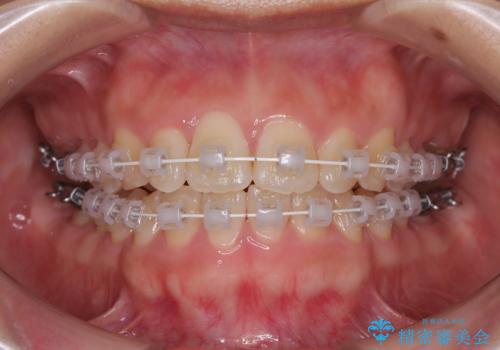

治療終了時

前歯が自然なアーチにきれいに並び、正中(上下の中心線)も整い、咬み合わせも良好です。

側方拡大することで、非抜歯であるにも関わらず前歯が前方に出ることなく、バランスの良い仕上がりとなりました。